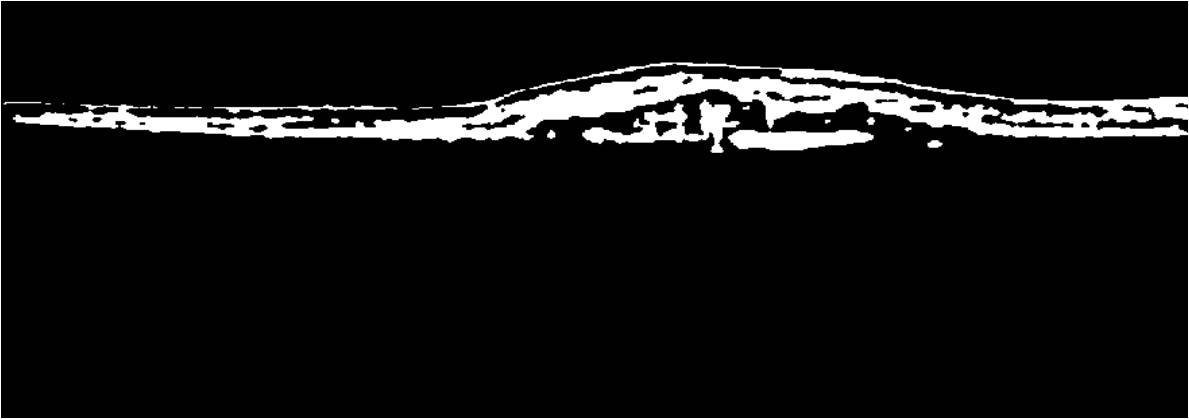

In Fig. 2, we observe that the absolute Fourier-domain representation of the noisy image (|ψ(I)|𝜓𝐼|\psi(I)|) has two prime components: the central frequency spectrum structure that contains information regarding the sub-retinal micro-structure (C𝐶C), and the extra frequency components occupying high-frequency regions that appear due to the additive noise (E𝐸E). Since the position of the frequency components in the Fourier-domain signify the sub-retinal components and the noise components, a binary image (ψ(I)superscript𝜓𝐼\psi^{\prime}(I)) can be generated from the Fourier domain representation of the noisy image ψ(I)𝜓𝐼\psi(I), such that ψ(I)=|ψ(I)|>0superscript𝜓𝐼𝜓𝐼0\psi^{\prime}(I)=|\psi(I)|>0, and ψ(I)=C+Esuperscript𝜓𝐼𝐶𝐸\psi^{\prime}(I)=C+E. For an ideal denoised image, the central frequency spectrum must be conserved while the extra frequency terms introduced by noise must be suppressed. The challenge of separating the noise components from the central frequency components lies in the fact that the exact position of the sub-retinal and noisy components in the absolute Fourier-domain representation are unknown and variable across images.

Refer to caption

Figure 2: Fourier-domain spectrum composition for OCT images. (a) Original noisy image (I𝐼I) (b) Binary image of the Fourier-domain representation (ψ(I)superscript𝜓𝐼\psi^{\prime}(I)). The region within the red box is the central frequency spectrum structure that contains information regarding the sub-retinal micro-structure. C𝐶C is an image with components within in the red box only and all other pixels outside the box are zero. All remaining high-frequency components outside the red box are high-frequency terms introduced by noise and are represented by image E𝐸E.